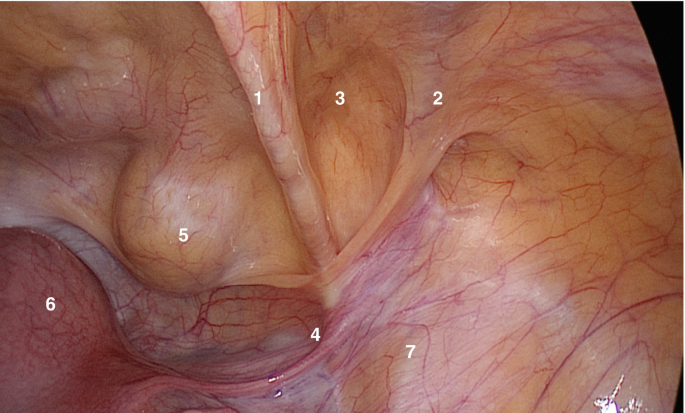

Inguinal Anatomy with Peritoneum Intact - Dr. R. Padmakumar

An initial intraperitoneal survey identifies anatomic landmarks, right... | Download Scientific Diagram